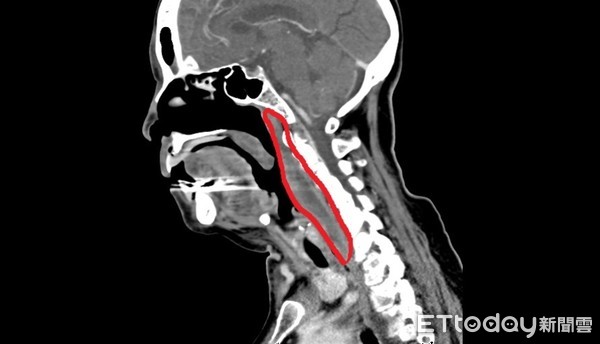

▲患者右側鼻咽、下咽有長條狀積膿,嚴重壓迫呼吸道。(圖/澄清醫院中港院區提供)

爾後醫師經電腦斷層證實,感染範圍從右側鼻咽、口咽,甚至延伸至下咽和甲狀腺旁空腔,其積膿體積有5公分 × 3公分,呈長條狀。徐毓婷醫師表示,由於該病患的膿瘍已壓迫到呼吸道,在經口顯微手術之前,先給予插管以保護呼吸道,順利將受到感染的腔室都打開,徹底進行清創引流。